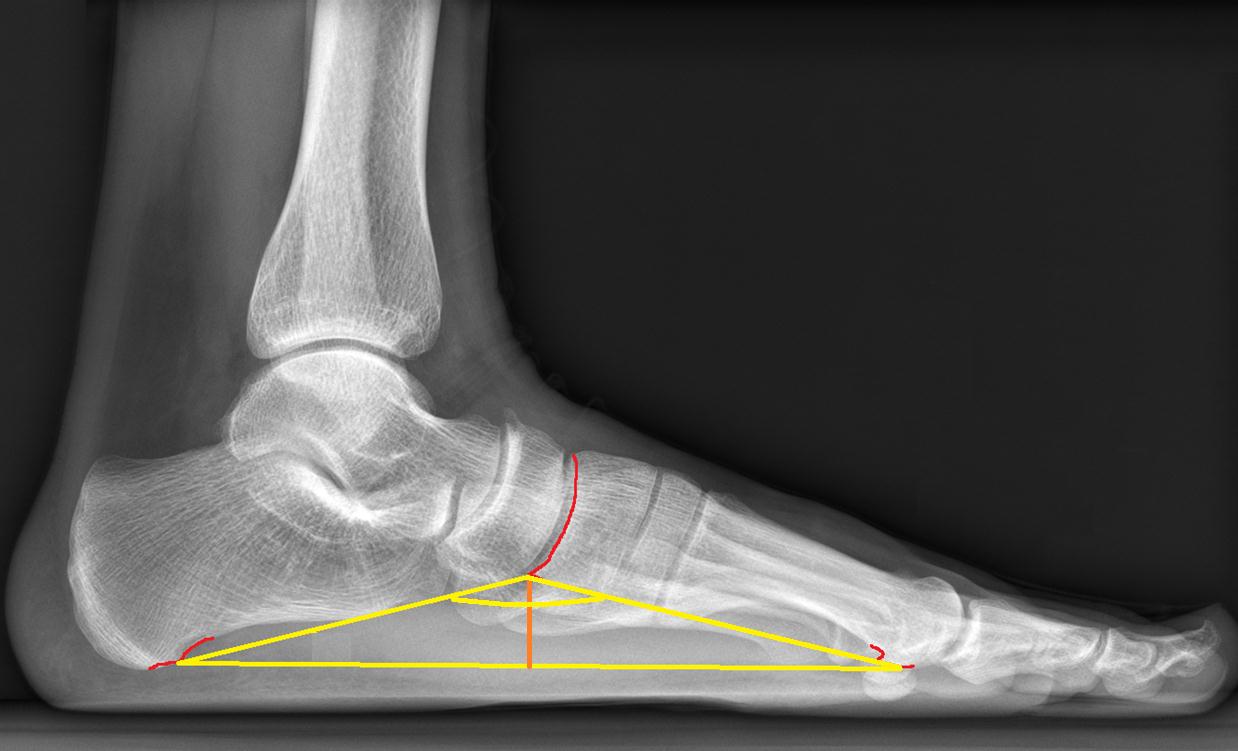

Рентген

Эта процедура при деформации стопы назначается врачом. Специалисты рекомендуют её детям, у которых невозможно диагностировать плоскостопие другими методами. Она также обязательна для медицинского освидетельствования юношей, подлежащих призыву. Процедура безопасна и не вызывает дискомфорта, так как облучение минимально. Результаты рентгеновского исследования интерпретирует врач.

Существует два типа рентгеновских снимков:

С прямой проекцией. Пациент ставит одну ногу на кассету с рентгеновской пленкой, а вторую поднимает. Можно держаться за стул или опираться на стену для получения качественного снимка с первого раза. Этот метод позволяет выявить поперечное плоскостопие. Существует три стадии данного заболевания: компенсация, субкомпенсация и декомпенсация.

С боковой проекцией. При таком снимке фиксируется весь голеностопный сустав, одна нога приподнимается. Этот рентген позволяет увидеть продольное плоскостопие и определить степень заболевания.

Указанные методы помогут установить наличие заболевания, его тип и степень плоскостопия. Однако для предотвращения болезни важно заниматься профилактикой: ходить босиком по неровным поверхностям, выполнять специальные упражнения и делать массаж стоп.

Одним из основных и самых точных методов при диагностике плоскостопия является рентгенография. Она не только обнаруживает патологию, но и определяет ее стадию и степень деформации. Снимки делают в положении стоя в двух проекциях (прямой и боковой). Они показывают расположение и состояние костей.